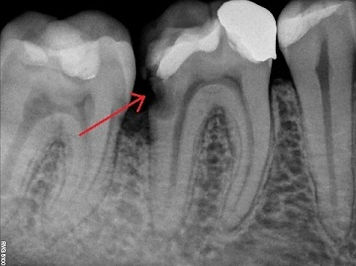

widoczny głęboki ubytek próchnicowy sięgajacy do miazgi zębowej konieczne leczenie kanałowe

Widoczne na RTG zmiany zapalne wokół wierzchołka, niedopełnione kanały